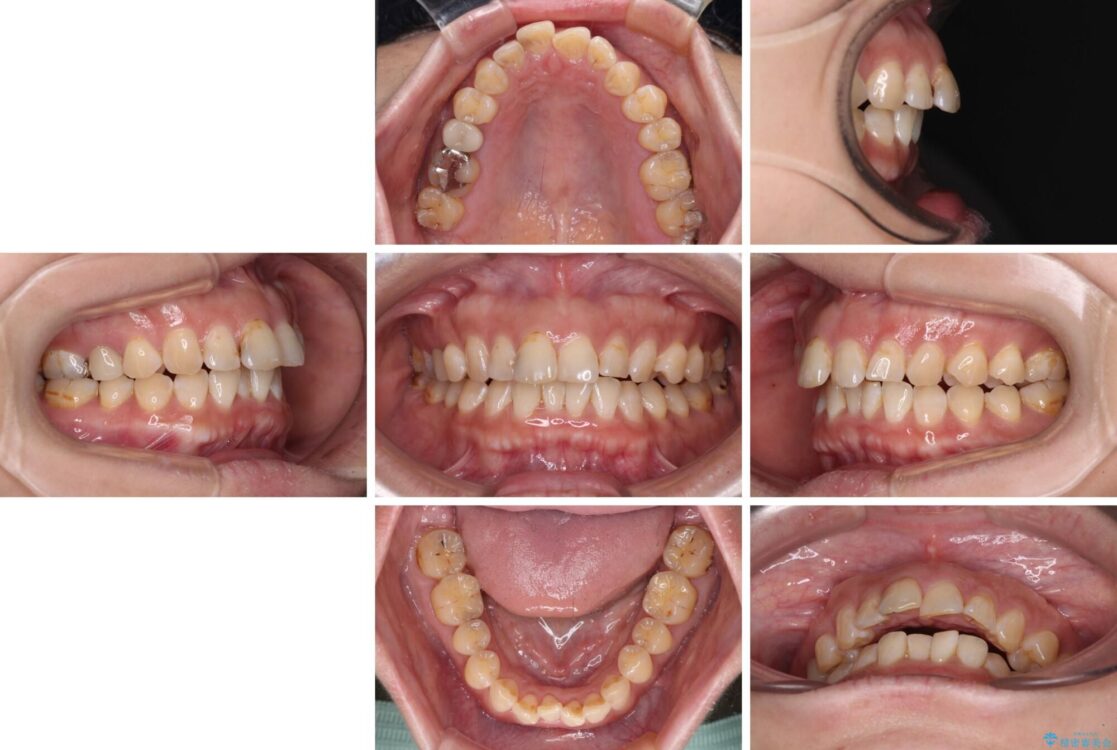

飛び出た上の前歯を気にして来院された患者様です。

奥歯の咬み合わせは、上顎歯列が理想的な一よりも数mm前方にある状態でした。

なるべく早めに治療を終えたいとのことで、補助装置を用いて上顎臼歯を後方に移動させ、同時にワイヤー装置にて整えることとしました。

治療前

• 【モニター】飛び出た前歯を整えたい ワイヤー矯正治療 治療前画像